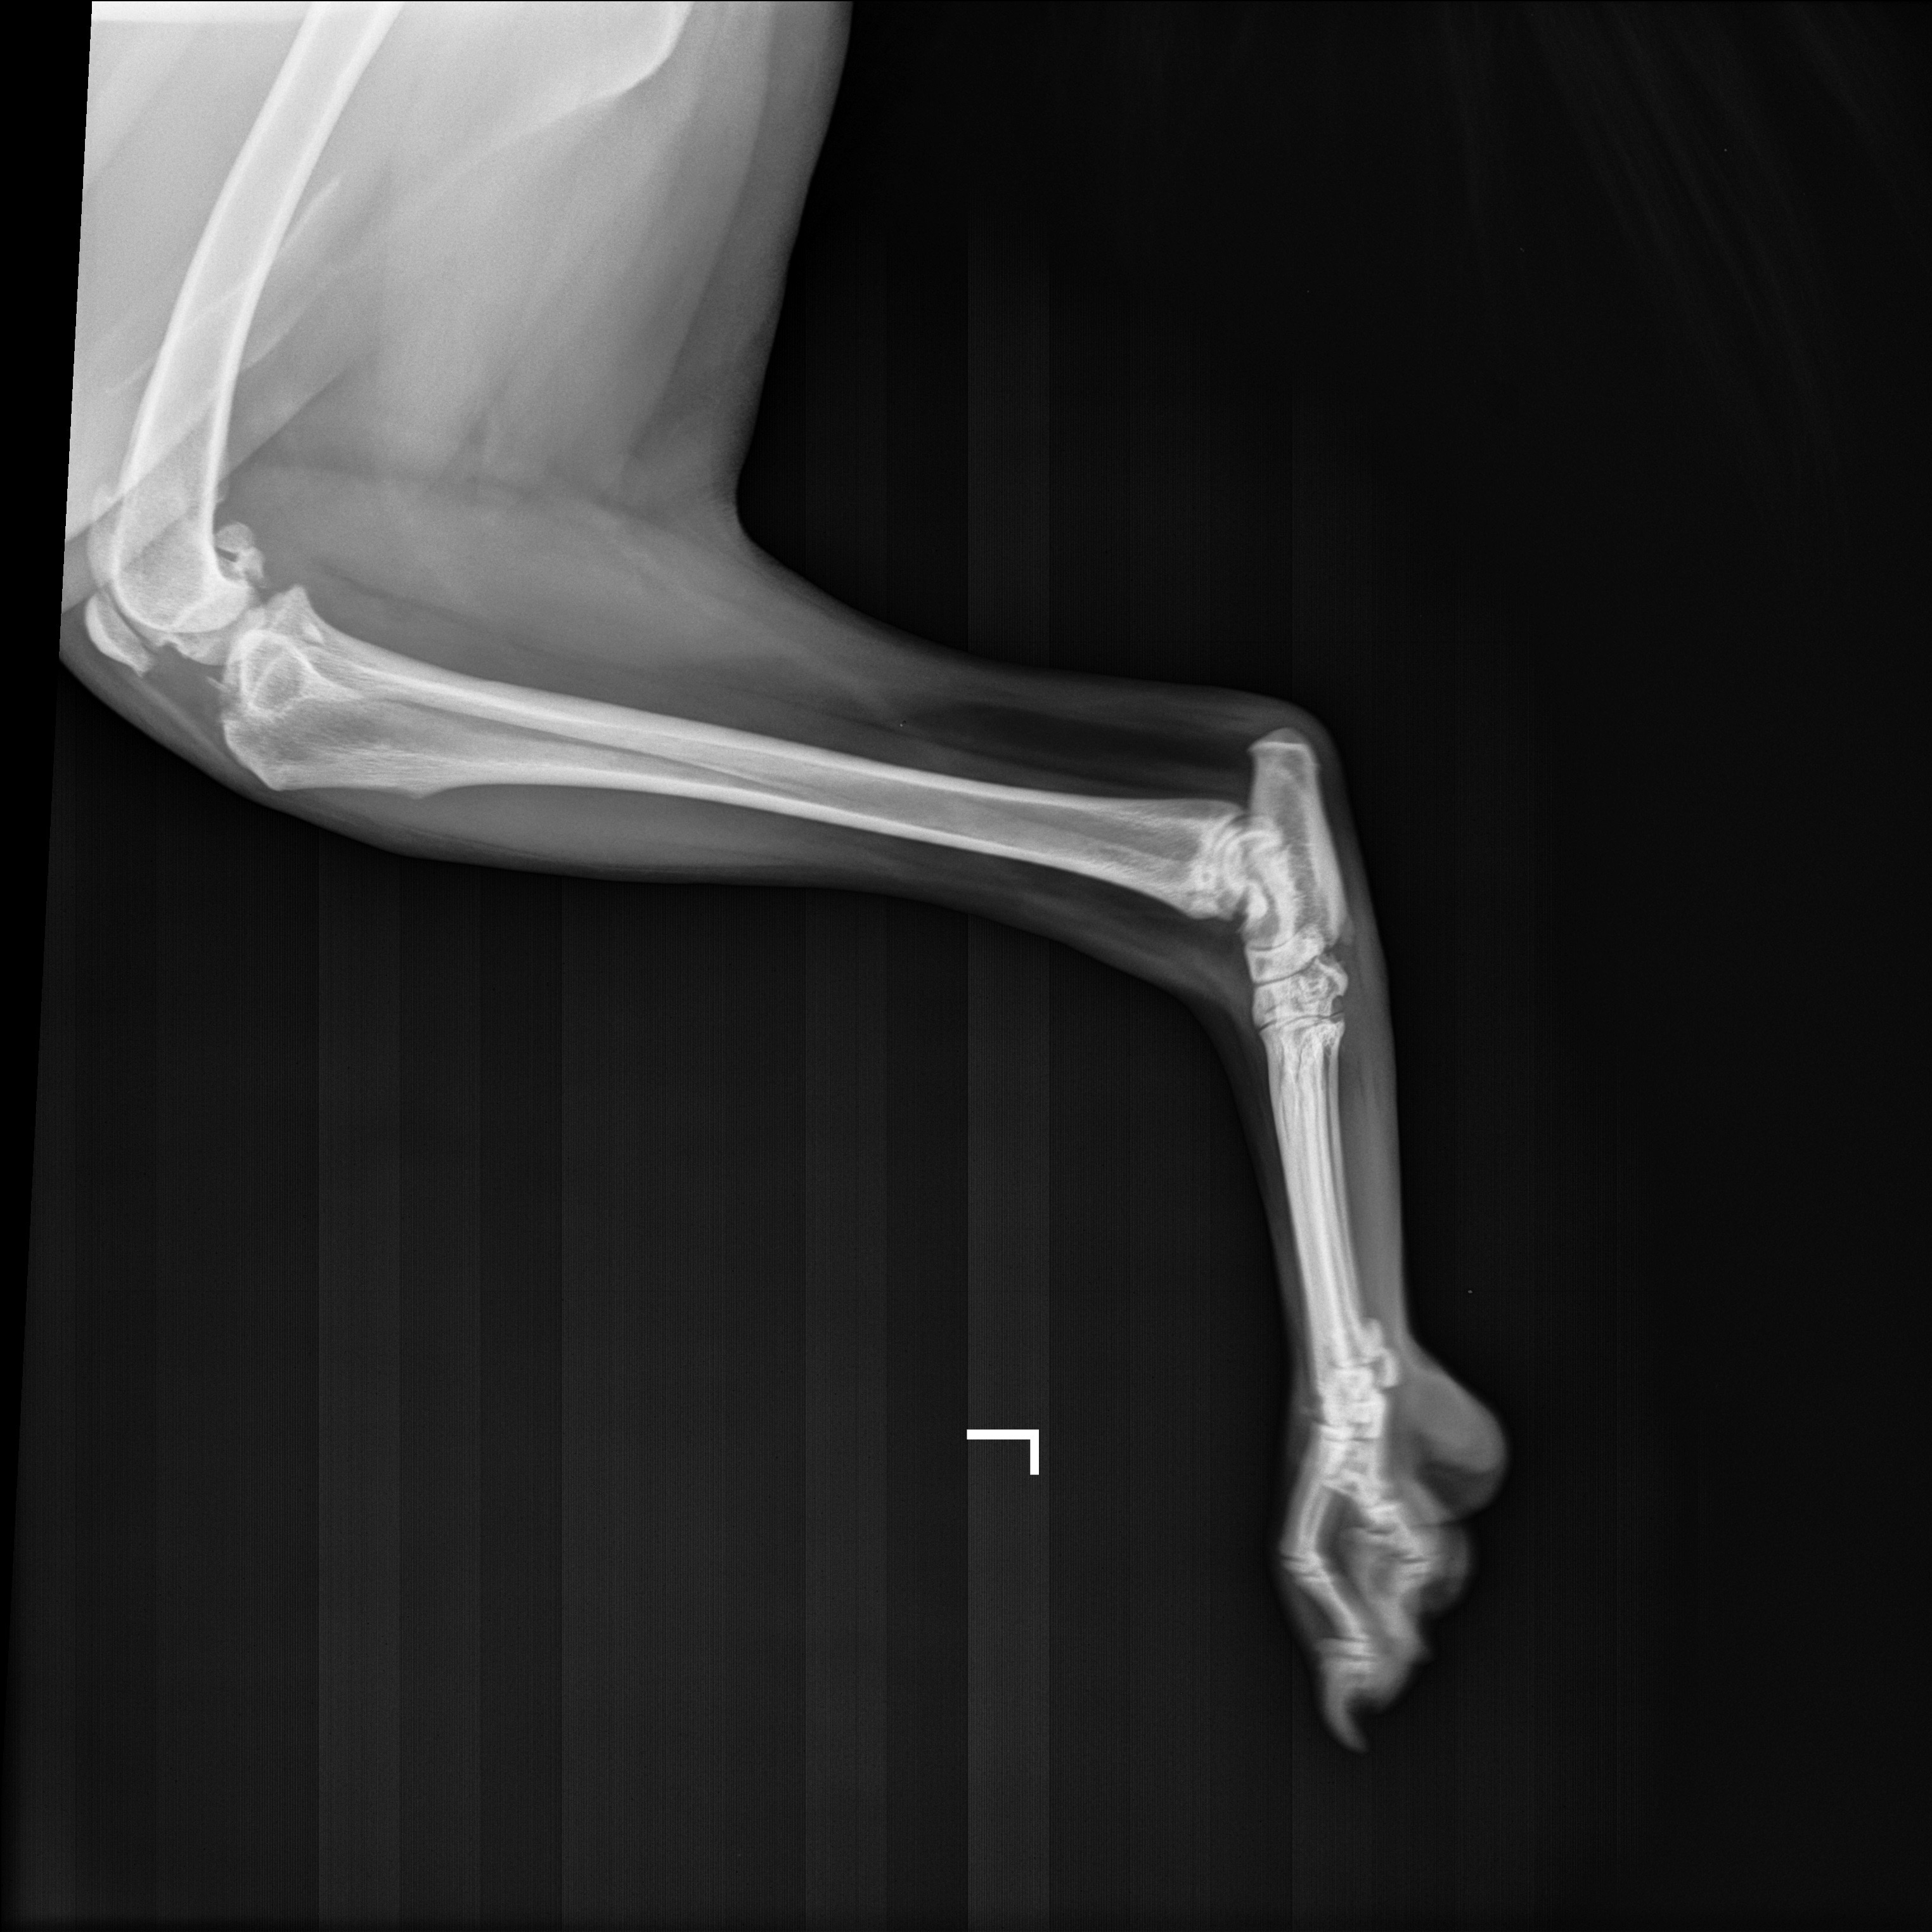

Zephyr has grown into a loyal, loving companion who goes everywhere with me. Over the past months, I started noticing Zephyr limping at times, and that’s when I took him to the vet to find out he would need knee surgery. He doesn’t understand why his body won’t let him do the things he loves most, and it breaks my heart to watch my best friend struggle.